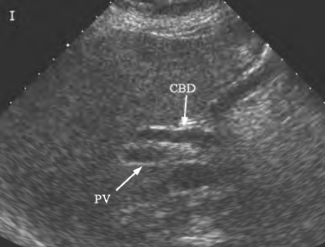

2.肝外胆管扩张,肝外胆管直径>8mm或其直径等于或大于与其平行的门静脉直径,超声显示“平行管征”或“双筒征”(图25-20)。

图25-20 肝外胆管扩张,“双筒征”(箭头所示)声像图